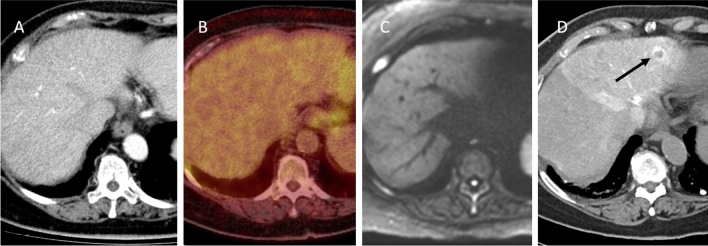

Fig. 4.

A intraprocedural transcatheter CTHA. B: follow-up 18F-FDG PET-CT 2,5 months after CTHA-guided ablation. Retrospectively, an enhancing ring lesion was identified in segment VII on the CTHA (arrowheads), which had not been noticed during the microwave ablation